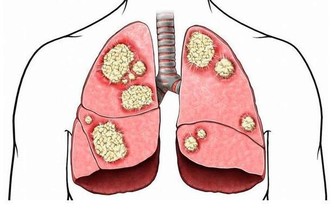

凌晨3-5點,肺的排毒。此即為何咳嗽的人在這段時間咳得最劇烈,

因排毒動作已走到肺;不宜用止咳藥,以免抑制廢積物的排除。